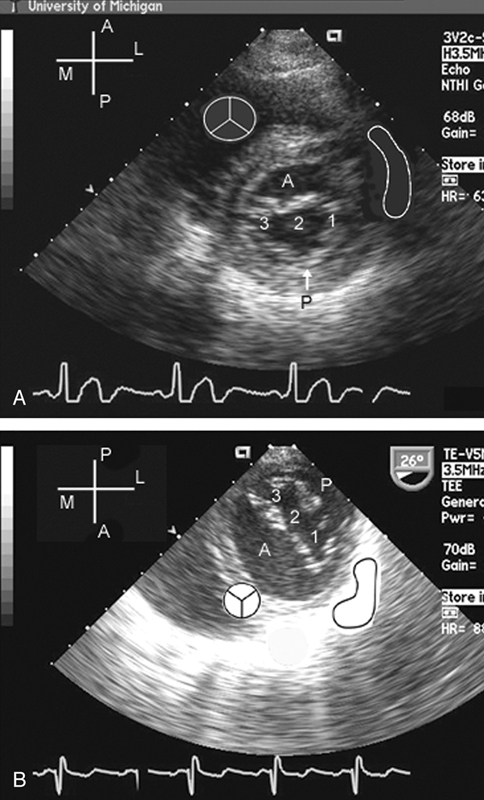

فحوصات تشخيصية لبعض امراض القلب والشرايين التاجية